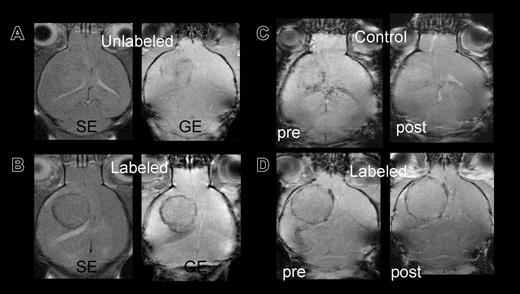

Control mice infused with unlabeled or killed FE-PLL-labeled cells did not develop a hypointense ring surrounding the tumor performed 10 or more days following RT2 cell implantation. Control versus labeled mice are shown in Figure 3A-B. One mouse that received killed labeled cells on day 3 following RT2 cell implantation had slight decrease in signal intensity around the tumor on day 12 after infusion of Sca1+ cells that was thought to be due to blood flow effects. To discriminate the signal intensity decrease because of slow venous blood flow from the susceptibility artifact for FE-PLL-labeled cells, Gd-DTPA was administered. An increase in signal intensity and disappearance of hypointense regions occurred following the infusion of Gd-DTPA in the mouse that received killed labeled Sca1+ cells, whereas the hypointense area remained in a mouse with FE-PLL-labeled viable cells (Figure 3C-D).

Control versus labeled mice: group 3 mice imaged at day 10 after cell transplantation. (A) Signal intensity in tumor of control mouse with unlabeled cells on either spin echo (SE) or gradient echo (GE) sequences are almost isointense with contralateral hemisphere. (B) Mouse receiving FE-PLL-labeled cells demonstrates clear ring at the tumor periphery on both SE and GE. (C-D) Post-Gd-DTPA contrast-enhanced MRIs to differentiate between slow blood flow in patent vessels at the tumors' edge and the presence of magnetically labeled cells. The hypointense area in a group 2 control mouse (C) that received killed labeled cells becomes isointense with surrounding brain after contrast, indicating the Gd-DTPA in the area increased the signal intensity, whereas the dark ring persists in the mouse with labeled cells (D).

The administration of a paramagnetic contrast agent may be helpful in differentiating areas of slow blood flow from vessels incorporating iron-labeled cells. Vasculature with labeled cell incorporation was observed to remain hypointense in the presence of a paramagnetic contrast agent, whereas the darkening near the tumor rim in a control mouse became isointense following the administration of Gd-DTPA (Figure 3C-D). The disappearance of the rim is an indication that the decrease in signal intensity observed in the control animal with killed labeled cells on precontrast images was due to slow blood flow. Of note, infusion of killed labeled cells should have been cleared from circulation shortly after they were administered early in tumor development (day 2) and thus could not respond to the chemotactic stimuli that induce the migration of cells to sites of ongoing angiogenesis. This result also indicates the susceptibility effect from iron-containing cells in the vasculature has a greater net effect on signal intensity than does the paramagnetic T1 and T2 shortening in the blood; thus, it is possible to use these in conjunction when indicated to detect areas of blood-brain barrier disruption or to measure tumor relative cerebral blood volume.18,19